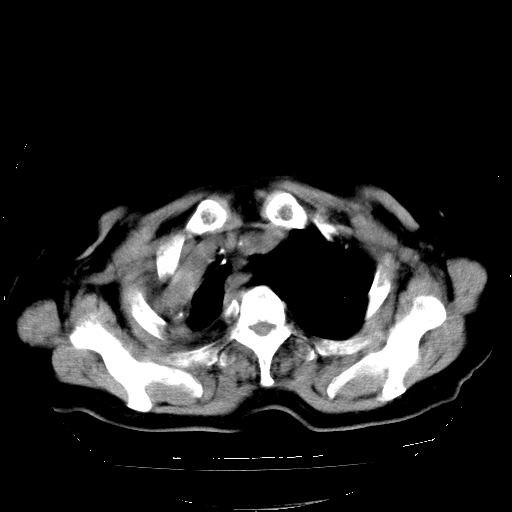

标题: CT23991:女,72岁,咳嗽、憋气一周。 [打印本页]

女,72岁,咳嗽、憋气一周,十年前曾患肺结核及胸膜结核。

1.右侧损毁肺伴胸膜钙化,2.左肺小结节灶,良性可能大,注意复查。3.肝脏左叶囊肿。4.先天性一侧肺不发育待出外(右侧胸廓无明显塌陷)。对比原片应该非常有帮助。